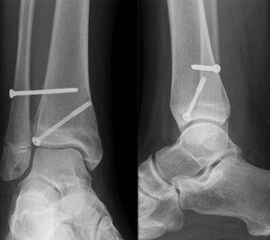

Behandlungsziel ist die exakte Rekonstruktion der Gelenkfläche sowie die Minimierung des Risikos einer späteren Wachstumsstörung. Dislozierte Frakturen werden offen reponiert, die Osteosynthese erfolgt mit einer Kleinfragmentschraube. Finden sich viele kleine Fragmente kann eine K-Draht Osteosynthese durchgeführt werden. Wird der Innenknöchel operiert, kann bei gleichzeitiger hochgradiger lateraler Instabilität eine Rekonstruktion des lateralen Bandapparats durchgeführt werden. Fibula Frakturen stellen sich meist spontan ein, sodass hier keine zusätzliche Osteosynthese notwendig ist.

Nach der Osteosynthese wird die Fraktur für ca. vier Wochen in einem Unterschenkelgips ruhiggestellt. Bei Schmerzfreiheit der Frakturzone erfolgt anschließend eine schmerzadaptierte Belastungssteigerung über weitere zwei Wochen. Sobald unter Alltagsbedingungen Beschwerdefreiheit besteht kann die sportliche Belastung langsam gesteigert werden. Kirschnerdrähte werden 6-8 Wochen postoperativ, Schrauben nach zwölf Wochen entfernt. Es empfiehlt sich klinische und radiologische Kontrollen im Abstand von 6 Monaten bis zum Wachstumsabschluss durchzuführen, um ein mögliches Fehlwachstum frühzeitig zu erkennen.